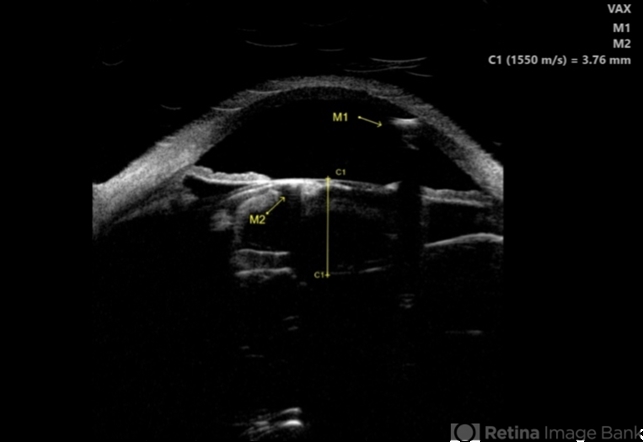

- intralenticular gas, pneumatic retinopexy, post-op

- Ultrasound biomicroscopy image of gas in the anterior chamber (A, M1) and lenticular cortex (A, M2) of a 68-year-old man following pneumatic retinopexy. Patient presented with a macula-off retinal detachment requiring vitrectomy, with pneumatic retinopexy done in office at post-operative week 1 to supplement poor gas fill.